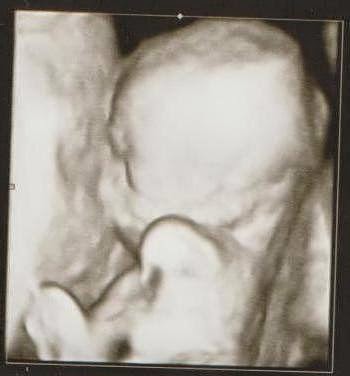

Confirmar que estaba embarazada por tercera vez fue una gran alegria. Descubrir que mi embarazo era monocorial triamniotico (una sola placenta y tres sacos) fue un shock durante un dia, preocupaciones y miedos durante meses y una inmensa felicidad por el resto de mi vida.

19 y 19+5

• 19 y 19+5